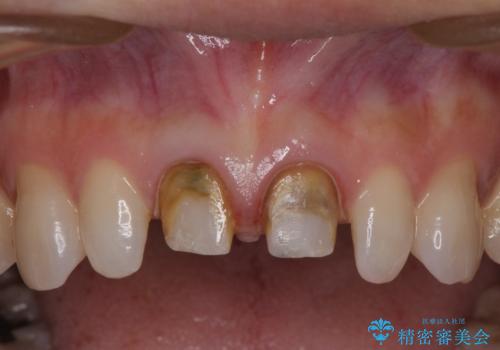

- 他院で奥歯に虫歯があると言われて、ご来院された患者様です。チェックしたところ、奥歯に虫歯は認められませんでした。

前歯に違和感や根尖病巣(根の先に細菌が溜まっている)が認められたため、治療をご提案しました。

患者様は、もともと奥歯の虫歯を心配してご来院されましたが、前歯に問題が見つかりました。

金属を使用したメタルボンドクラウンが入っていたため、いつかオールセラミックにしたいときに根管治療も行ったほうが良いとご提案し、今回行いました。

歯と歯肉の境目の色は、歯自体が黒くなっている場合、完全にカバーすることは難しいです。